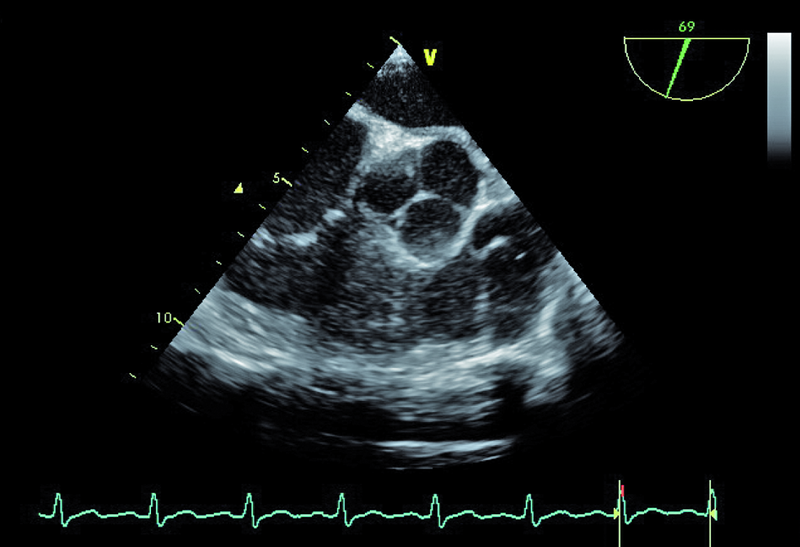

W badaniu echokardiograficznym zwrócono uwagę na powiększenie jamy lewej komory z nieznacznie upośledzoną kurczliwością mięśnia (ryc. 1). Stwierdzono także trójpłatkową zastawkę aortalną (ryc. 2) ze śladową niedomykalnością oraz małą niedomykalność mitralną. Te nieprawidłowości nie mogły tłumaczyć szmeru ciągłego w badaniu fizykalnym ani też nieznacznie powiększonej sylwetki serca. Przyczyną szmeru ciągłego jest najczęściej przetrwały przewód tętniczy Botalla, łączący aortę i pień płucny. Połączenia takiego jednak w miejscu typowym nie znaleziono. Rejestrowano u chorego prawidłową średnicę pnia płucnego (ryc. 3) oraz nieznacznie przyspieszoną prędkość wypływu płucnego (ryc. 4). Szmer ciągły nakazywał poszukiwać innych rzadkich połączeń między dużymi naczyniami. Jedną z nich jest okienko aortalno-płucne, czyli tzw. fenestracja aortalno-płucna, i tę wadę właśnie rozpoznano u chorego.